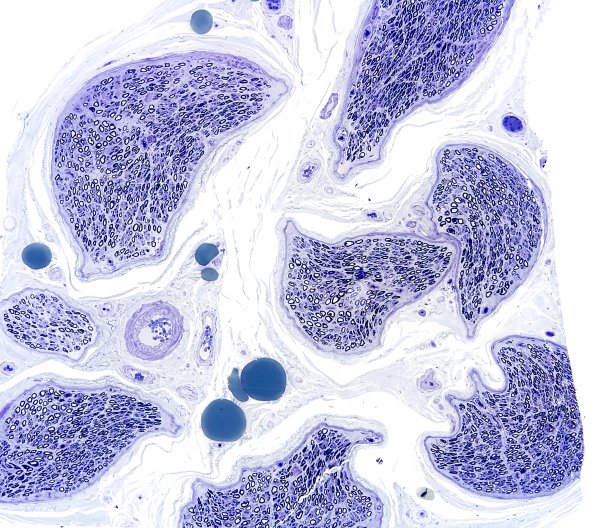

Washington University Experience | PERIPHERAL NEUROPATHY | 0 PNS ARTIFACTS | 6A1 Artifact, hyperosmolar Plastic 1A

6A1,2 These are shrunken fascicles which are the result of hyperosmolar fixative. (Toluidine blue stained one micron thick plastic embedded sections)